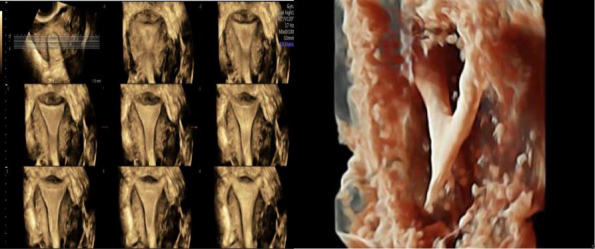

再者,对于妇科,我们可以评估子宫的整个宫腔形态、宫腔病变、子宫的内膜体积、节育器形状、卵巢体积、卵泡的大小和数量等。

输卵管造影评估输卵管的通畅性

子宫三维宫腔形态成像,可直观判断子宫畸形及宫腔内病变。